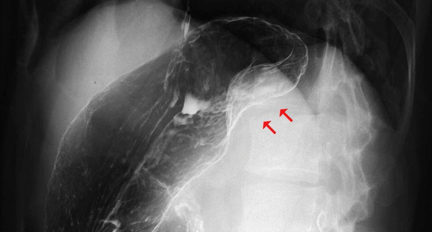

A 38-year-old man without any symptoms was found to have a splenic mass on routine medical examination. Physical examination found nothing remarkable. Laboratory test results were within normal limits. Tumor marker levels were not elevated (CEA: 1 ng/ml, AFP: 2 ng/ml, CA19-9: 2 ng/ml). Upper gastrointestinal (GI) series revealed extrinsic compression of the upper body of the stomach (Figure 1). An abdominal computed tomography (CT) scan revealed a 5-cm tumor and progressive delayed enhancement in the hilus of the spleen (Figure 2). Abdominal magnetic resonance imaging (MRI) revealed that the tumor was isointense on a T1-weighted image and hypointense on a T2-weighted image (Figure 3). The findings were confirmed by abdominal ultrasonography and we subsequently followed the patient by clinical and radiological examination. CT scan showed that the tumor was not enlarged four months after the initial presentation. It was thought that there was little possibility of malignancy, but on patient's request laparoscopic splenectomy was performed for diagnosis.

Figure 1: Upper GI series revealed extrinsic compression of the upper body of the stomach (arrow).